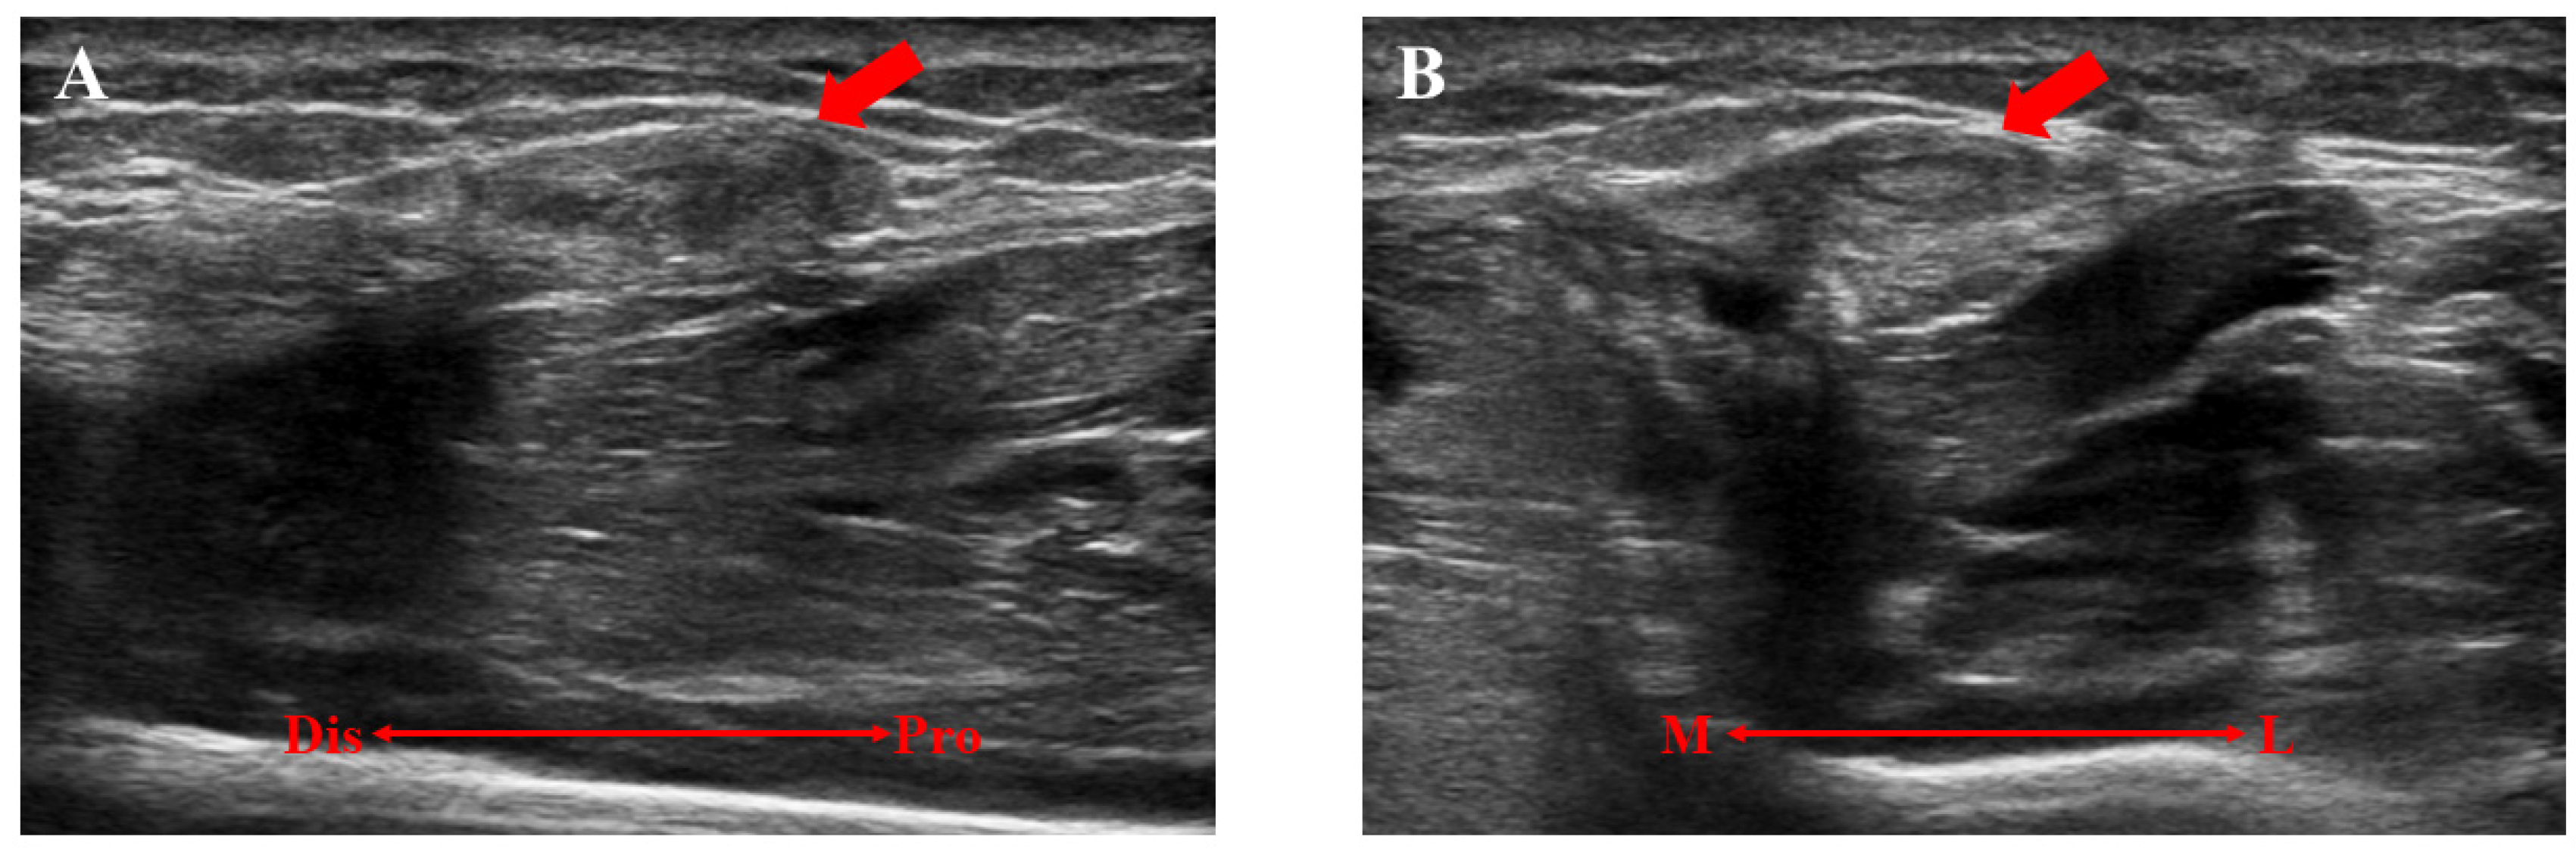

A 16-year-old baseball player was referred to our hospital for the assessment of multiple swelling lesions in the bilateral anterolateral lower legs. He had suffered from painful lesions when playing baseball for about a year, limiting his athletic performance. He had no history of traumatic injuries to the lower legs. Clinical examinations showed bilateral painful swelling lesions (1 on the right and 3 on the left) after dashing (Figure 1). These lesions were concave on palpation at rest. Ultrasonographically, these lesions did not swell with the patient in the supine position but were prominent in the standing position following dashing (Figure 2). Magnetic resonance imaging (MRI) showed a thin or void crural fascia (Figure 3). The preoperative visual analog scale (VAS) was 6/10 when the lesions were symptomatic. The patient was diagnosed with bilateral TAMHs.

Figure 2. A preoperative ultrasonographic evaluation of the left lower extremity. (A) The lesion was not detectable with the patient in the supine position. (B) The lesion (red arrow) was swollen and detectable in the standing position after strenuous activity. Dis, distal; Pro, proximal.